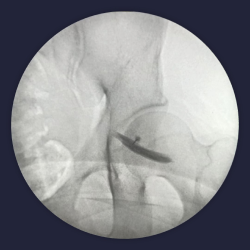

Intra op fluoroscopy images of piriformis injection

image 890

Contrast dye spread of piriformis